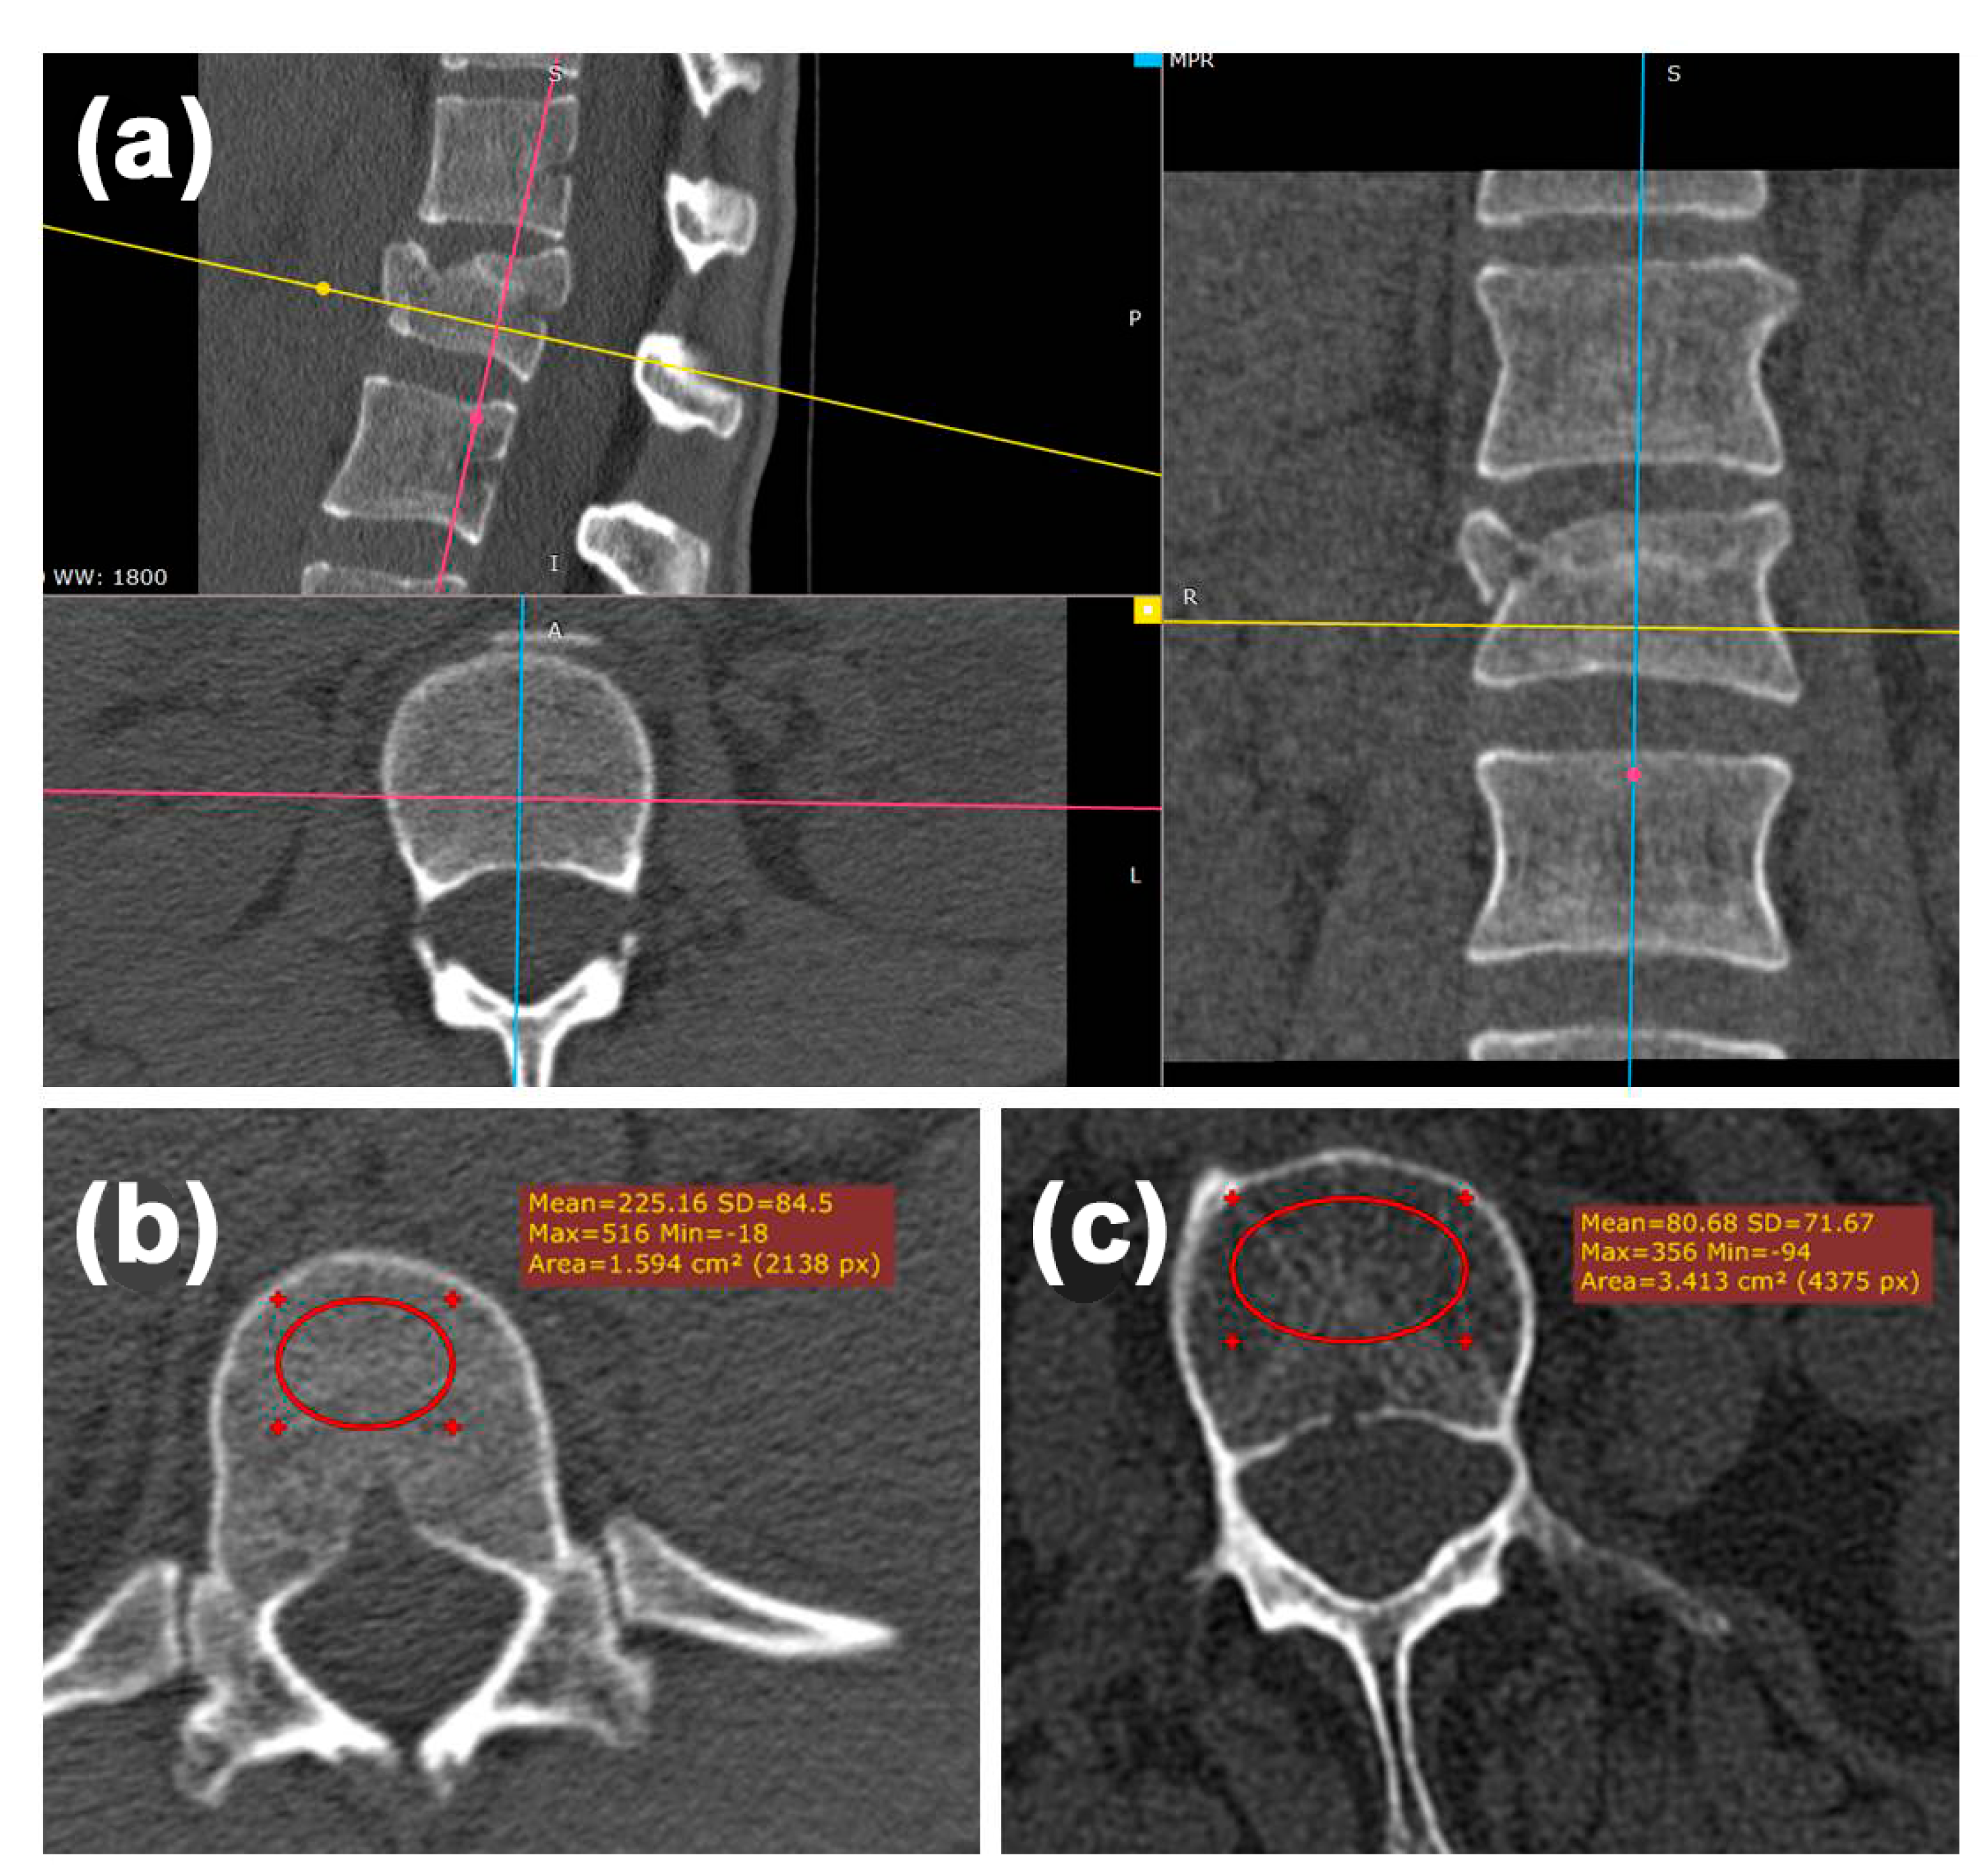

2.2. Morphological Analysis—Bulging

2.3. Radiologic Analysis—Hounsfield Units (HU)